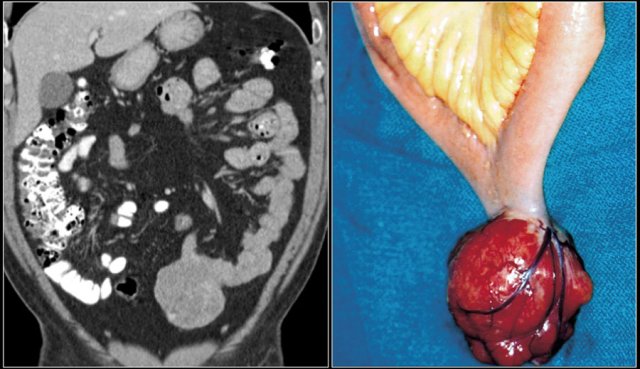

Gastrointestinal stromal tumors are mesenchymal tumors and represent 9% of all small bowel tumors.

These tumors most frequently occur in the stomach, followed by jejunum and ileum.

Occurrence in colon, rectum, esophagus and appendix is rare.

About 20-30 % of GIST's are malignant at presentation.

In the small bowel they are more often malignant than in the stomach.

Tumors smaller than 2 cm are usually benign, whereas masses larger than 5 cm are often malignant.

Malignant GIST's predominantly grow extraluminally and can show necrosis, hemorrhage, calcification (post therapy) and fistula formation.

Typically a GIST is a well defined and exophytic mass with heterogeneous enhancement and a clear delineation from the mesentery.

An intraluminal mass is far less common.

Obstruction is rare because GISTs do not involve the circumferential bowel wall, in contrast to adenocarcinoma.

Unlike carcinoid tumors, the primary lesion in a GIST is large.

Both GIST and lymphoma can show aneurysmal dilation of the bowel.

Liver metastases are usually hypervascular and can be missed on a single portal venous phase CT.

Lymph node metastases are generally not seen.

If lymphadenopathy is seen, you should consider another diagnosis.

Disease recurrence in resected GIST showing hypodense livermetastases and a large heterogeneous peritoneal metastasis.